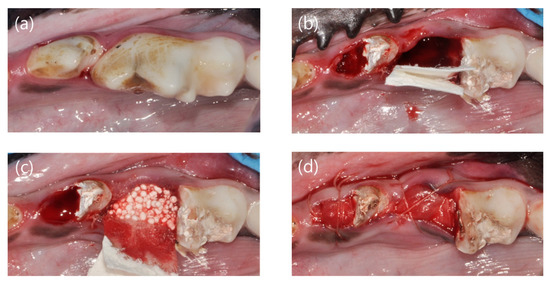

Figure 2.

Clinical photographs showing the experimental procedures. (a) Before surgery, (b) mesial root extraction and membrane application, (c) bone graft material application, and (d) suture.

Research manuscripts reporting large datasets that are deposited in a publicly available database should specify where the data have been deposited and provide the relevant accession numbers. If the accession numbers have not yet been obtained at the time of submission, please state that they will be provided during review. They must be provided prior to publication of general anesthesia was performed by intravenous injection of Zoletil (0.1 mg/kg; Virbac, Carros, France), Rompun (2.3 mg/kg; Bayer Korea, Ansan, Korea), and atropine sulfate (0.05 mg/kg; Jeil, Daegu, Korea). In addition, local anesthesia was performed by injecting 1:100,000 epinephrine-containing lidocaine (Huons Co. Ltd., Seongnam, Korea). Periapical radiograph was taken before surgery. The mandibular fourth premolar (P4) and first molar (M1) were hemisected using a diamond bur, and the mesial root was extracted. Root canal treatment was performed on the remaining distal root, and the cavity was filled with intermediate restorative material (IRM, Dentsply, York, PA, DE, USA) (Figure 2). Alveolar ridge preservation was performed using a synthetic bone graft (Biphasic calcium phosphate sphere; HansBiomed, Seoul, Korea). A resorbable non-crosslinked collagen membrane (Bio-Gide; Geistlich, Wolhusen, Switzerland) was applied randomly using a single-layer (control group) or double-layer (test group) technique. Thereafter, suture was performed with 4/0 vicryl, and periapical radiograph was taken (Figure 3).